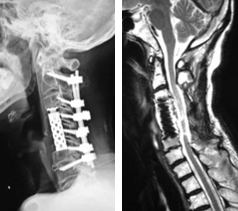

頚椎後方除圧固定術

対象となる疾患は、頚椎症性脊髄症、頚椎後縦靭帯骨化症、頚椎椎間板ヘルニア、脊椎腫瘍などです。頚椎後方除圧固定術は、頚椎の後方からアプローチして、圧迫因子となっている骨や靭帯を削除したり、金属製のスクリューなどで頚椎を固定する手術法です。頚椎に不安定性があったり、後弯と言って骨の並びが後ろに弯曲している場合などで有効な手術法となります。通常、手術翌日より座位や歩行訓練を行います。術後は、頚部を固定する装具を約1−3カ月装着します。

手術前のCTおよびMRIでは、椎体の後ろにある骨化した後縦靭帯が脊柱管内に大きく占拠し、脊髄を強く圧迫しています。

前方から椎体切除および骨化巣の浮上術を行い、代わりに金属製のケージを設置しました。非常に高度な狭窄であったため、後方からも除圧を追加し、頚椎のカーブを維持するためにスクリューとロッドによる固定を行いました。術後、神経症状は著明に改善しています。